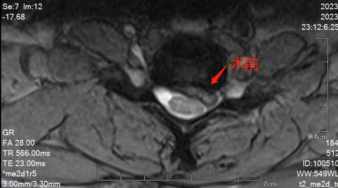

患者术前与术后的颈椎情况对比